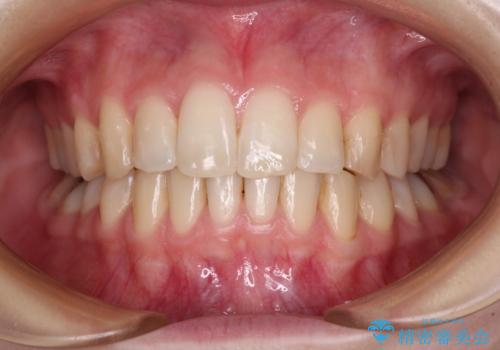

全ての奥歯の銀歯をセラミックに メタルフリー治療

途中体調を崩されてしまい、その間に仮歯が外れてしまうなど、治療期間が長引いてしまいました。

治療期間はかかってしまいましたが、念願のメタルフリーとなり、患者様には大変満足していただきました。